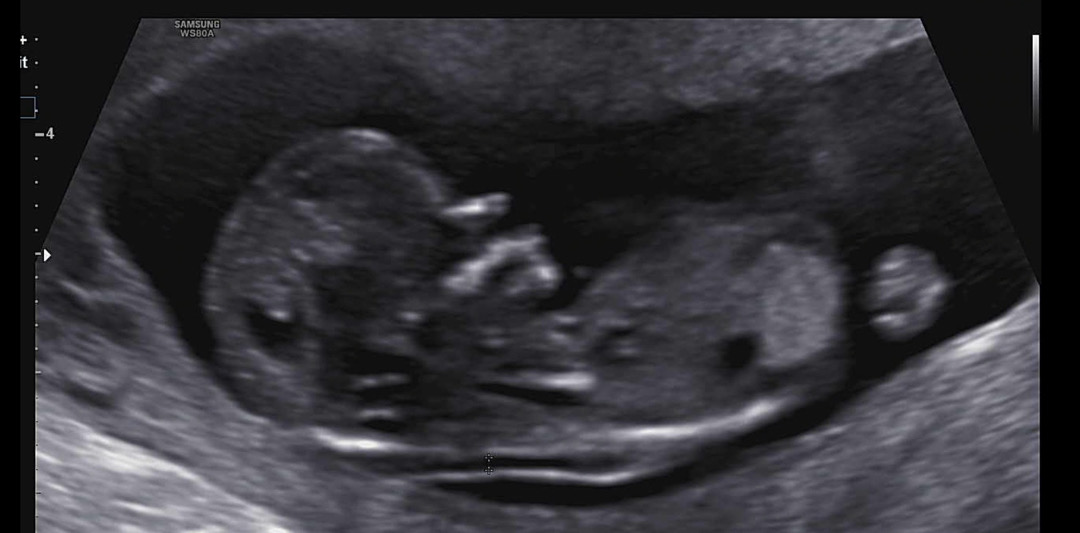

12주 1일 각도법... 문의 드려요!

딸일까요 아들일까요.....!!! 재미로..!!! ㅋㅋㅋㅋㅋ